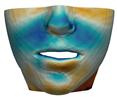

3.3. Simulation Error and Performance

4.1. Analysis of Simulation Accuracy

- Chin. Overall, the amount of error at the chin area is very low. This could be explained by the fact that the skin at the chin is very thin, and the coupling to the mandible makes the simulation highly predictive.

- Lips. In other regions, such as the lips, skin slides strongly over the underlying bones and teeth, and the deformation result is more difficult to predict. Overall, we observe higher variability in the error at the lips, and also some patients with higher error.

- Nose. The quality of the prediction of the deformation of the nose varies strongly across patients. In this case, the variability may depend on the type of surgery performed on each patient’s anterior nasal spine. This type of surgery is not easy to identify in the post-operative CBCT image due to the presence of bone grafts or fixation plates.

- Neck. Finally, we observe large error in the neck area (e.g., patients M5 and M8), and specifically at the junction point between the submental area and the neck (“C point” or “cervical point” in cephalometric analysis). This error was accounted for in our quantitative analysis, which negatively biased the overall results. However, this area is not of special interest to orthognathic surgeons. The deformation is known to be produced by a retraction of skin after surgery, but surgeons do not account for this effect during pre-operative planning.